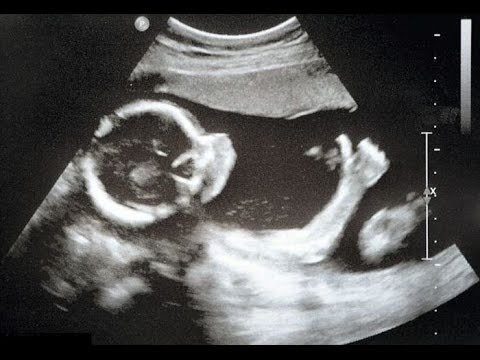

4. Пинки ощущаются через девять недель

Чувство трепетания в животе на ранних стадиях беременности является признаком движений ребенка. Движения начинаются примерно на седьмой неделе беременности, что очень рано для ожидающей матери, чтобы почувствовать их. Как правило, дети начинают пинать после девяти недель беременности, когда они начинают двигать конечностями. Ранние удары могут быть обнаружены во время ультразвукового сканирования. После 24 недель беременности, вы можете чувствовать удары ногами ребенка и довольно часто.